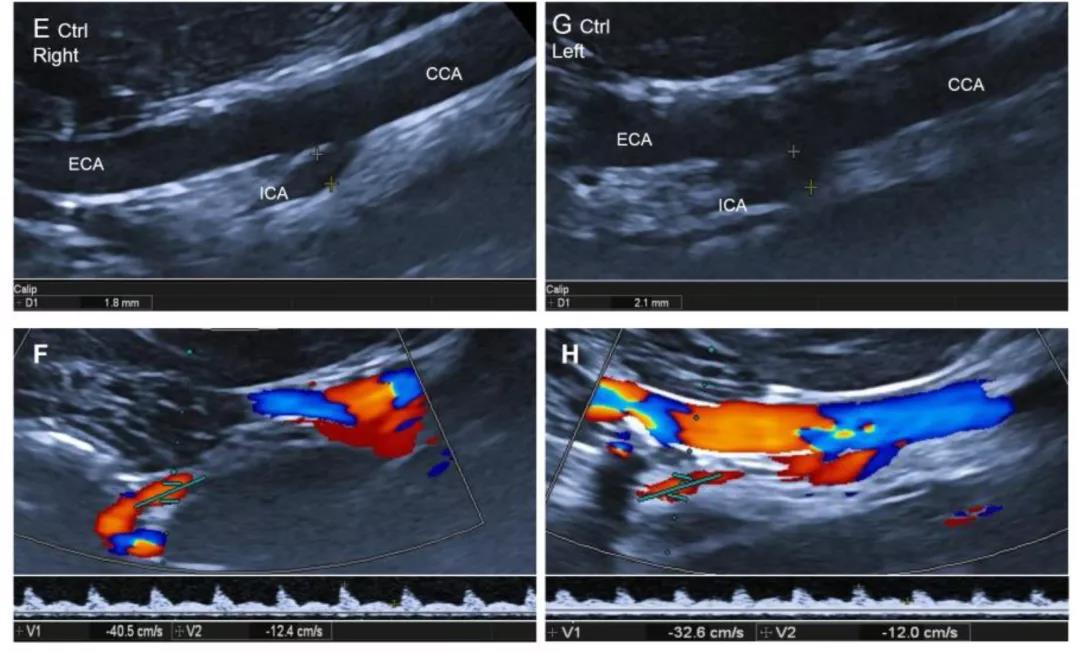

通过进一步对其进行磁共振 (MRI) 以及超声检测分析,显示ApoE基因编辑敲除犬脑部多处出现由于动脉粥样硬化导致的明显缺血性梗塞,颈内动脉出现明显斑块以及血管狭窄现象。

ApoE基因编辑敲除犬出现脑部明显缺血性梗塞,颈内动脉斑块以及血管狭窄现象(1)

ApoE基因编辑敲除犬出现脑部明显缺血性梗塞,颈内动脉斑块以及血管狭窄现象(2)